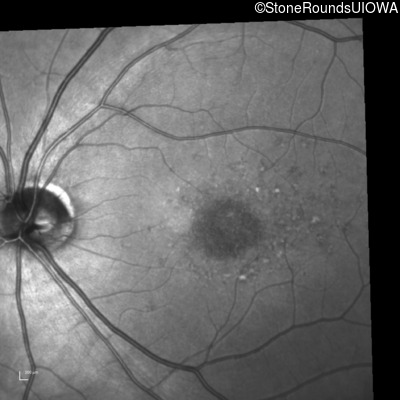

Blue Autofluorescence - Right - 20/80 -1

Exemplar